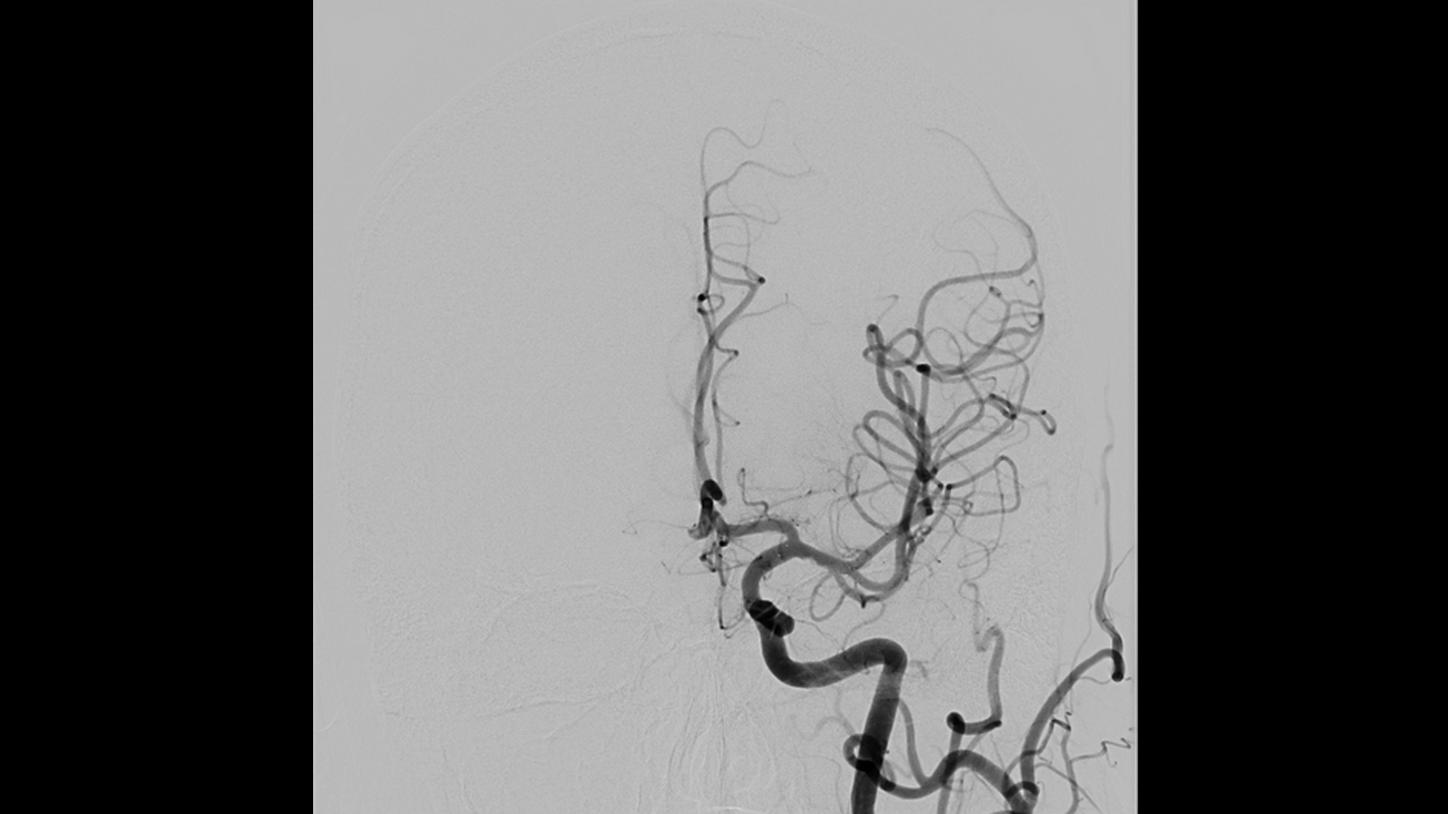

ARTIS icono biplane – A breakthrough in neuro-interventions

ARTIS icono biplane – a breakthrough in neuro interventions. See how ARTIS icono biplane is pushing boundaries in interventional neuroradiology and stroke care.

ARTIS icono biplane – Prof. Chapot in clinical use

Find out what your peers say. René Chapot, MD, shares his clinical experience with ARTIS icono biplane in interventional neuroradiology.